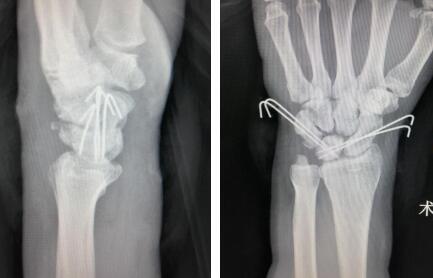

内固定

术后即刻